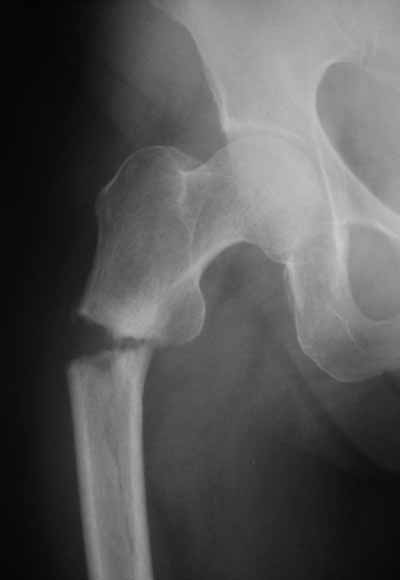

Присоединяюсь. Хотя посмотреть бы вторую проекцию.

Да? Качество рентгенограмм конечно неочень, но ведь это нестабильный перелом 31.А2.2, не так ли?